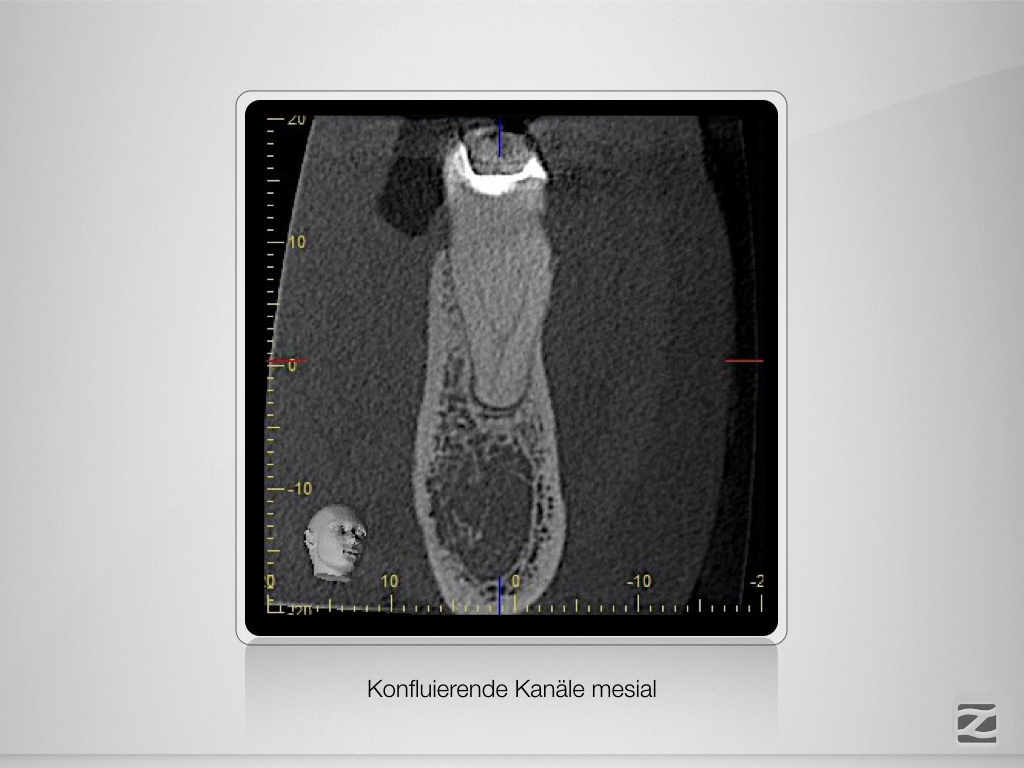

Planung leicht gemacht